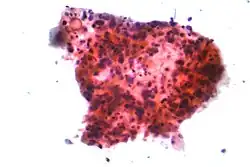

_by_core_needle_biopsy.jpg)

În cazul unui cancer bronho-pulmonar microcelular (CBPM), celulele conțin granule neurosecretoare dense (veziculecare conțin hormoni neuroendocrini), ceea ce îi conferă acestei tumori o asociere cu sindromul endocrin/paraneoplazic.[50] Majoritatea cazurilor apar în căile respiratorii mai mari (bronhiile primare și secundare]).[13] Aceste cancere se dezvoltă rapid și se extind la începutul bolii. 60-70 % dintre cazuri prezintă metastaze. Acest tip de cancer pulmonar este puternic asociat cu fumatul.[4]